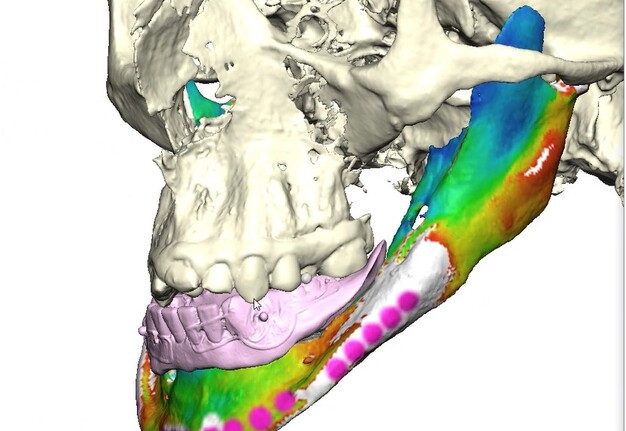

Records for this patient were collected using a dual-scan CBCT and intraoral scanning. A surgical planning session was completed with KLS Martin for the fabrication of a CAD-CAM subperiosteal implant system with immediate loading of a mandibular prototype (Figs 2-5).

A 3D-printed mandibular model with the subperiosteal system and prototype in place was also fabricated (Figs 6 and 7).